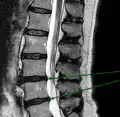

L'imagerie par résonance magnétique peut montrer la hernie, le canal vertébral, les nerfs, les tissus environnants. Les tissus mous sont les mieux analysés par cet examen qui est le plus performant pour le diagnostic de hernie discale. Les images pondérées en T2 montrent clairement la hernie.

IRM cervicale sagittale montrant une hernie discale de niveau C5-C6.